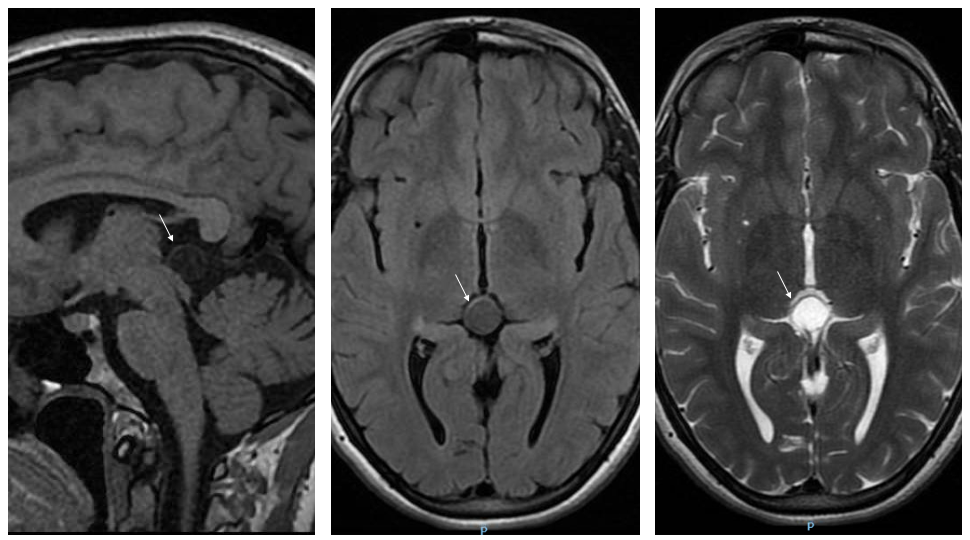

Además, en algunas ocasiones, el trastorno del sueño es la primera manifestación de una enfermedad más compleja, por ejemplo, de una enfermedad de Parkinson, por lo que su correcta identificación nos permite anticiparnos al diagnóstico de la enfermedad subyacente, cuyos síntomas más conocidos pueden aparecer años después.